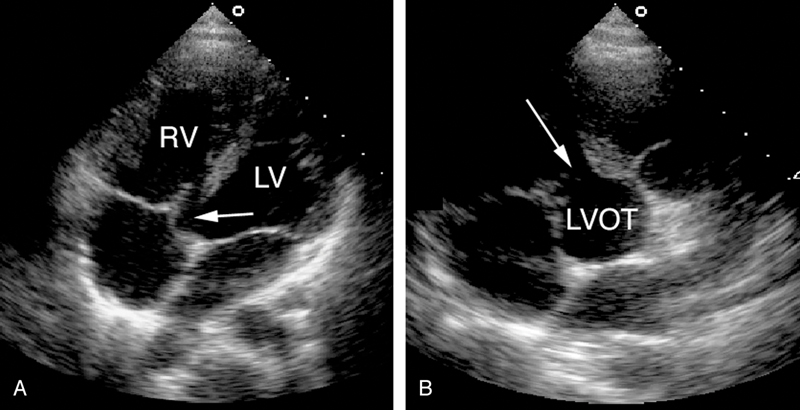

فحوصات تشخيصية لبعض امراض القلب والشرايين التاجية